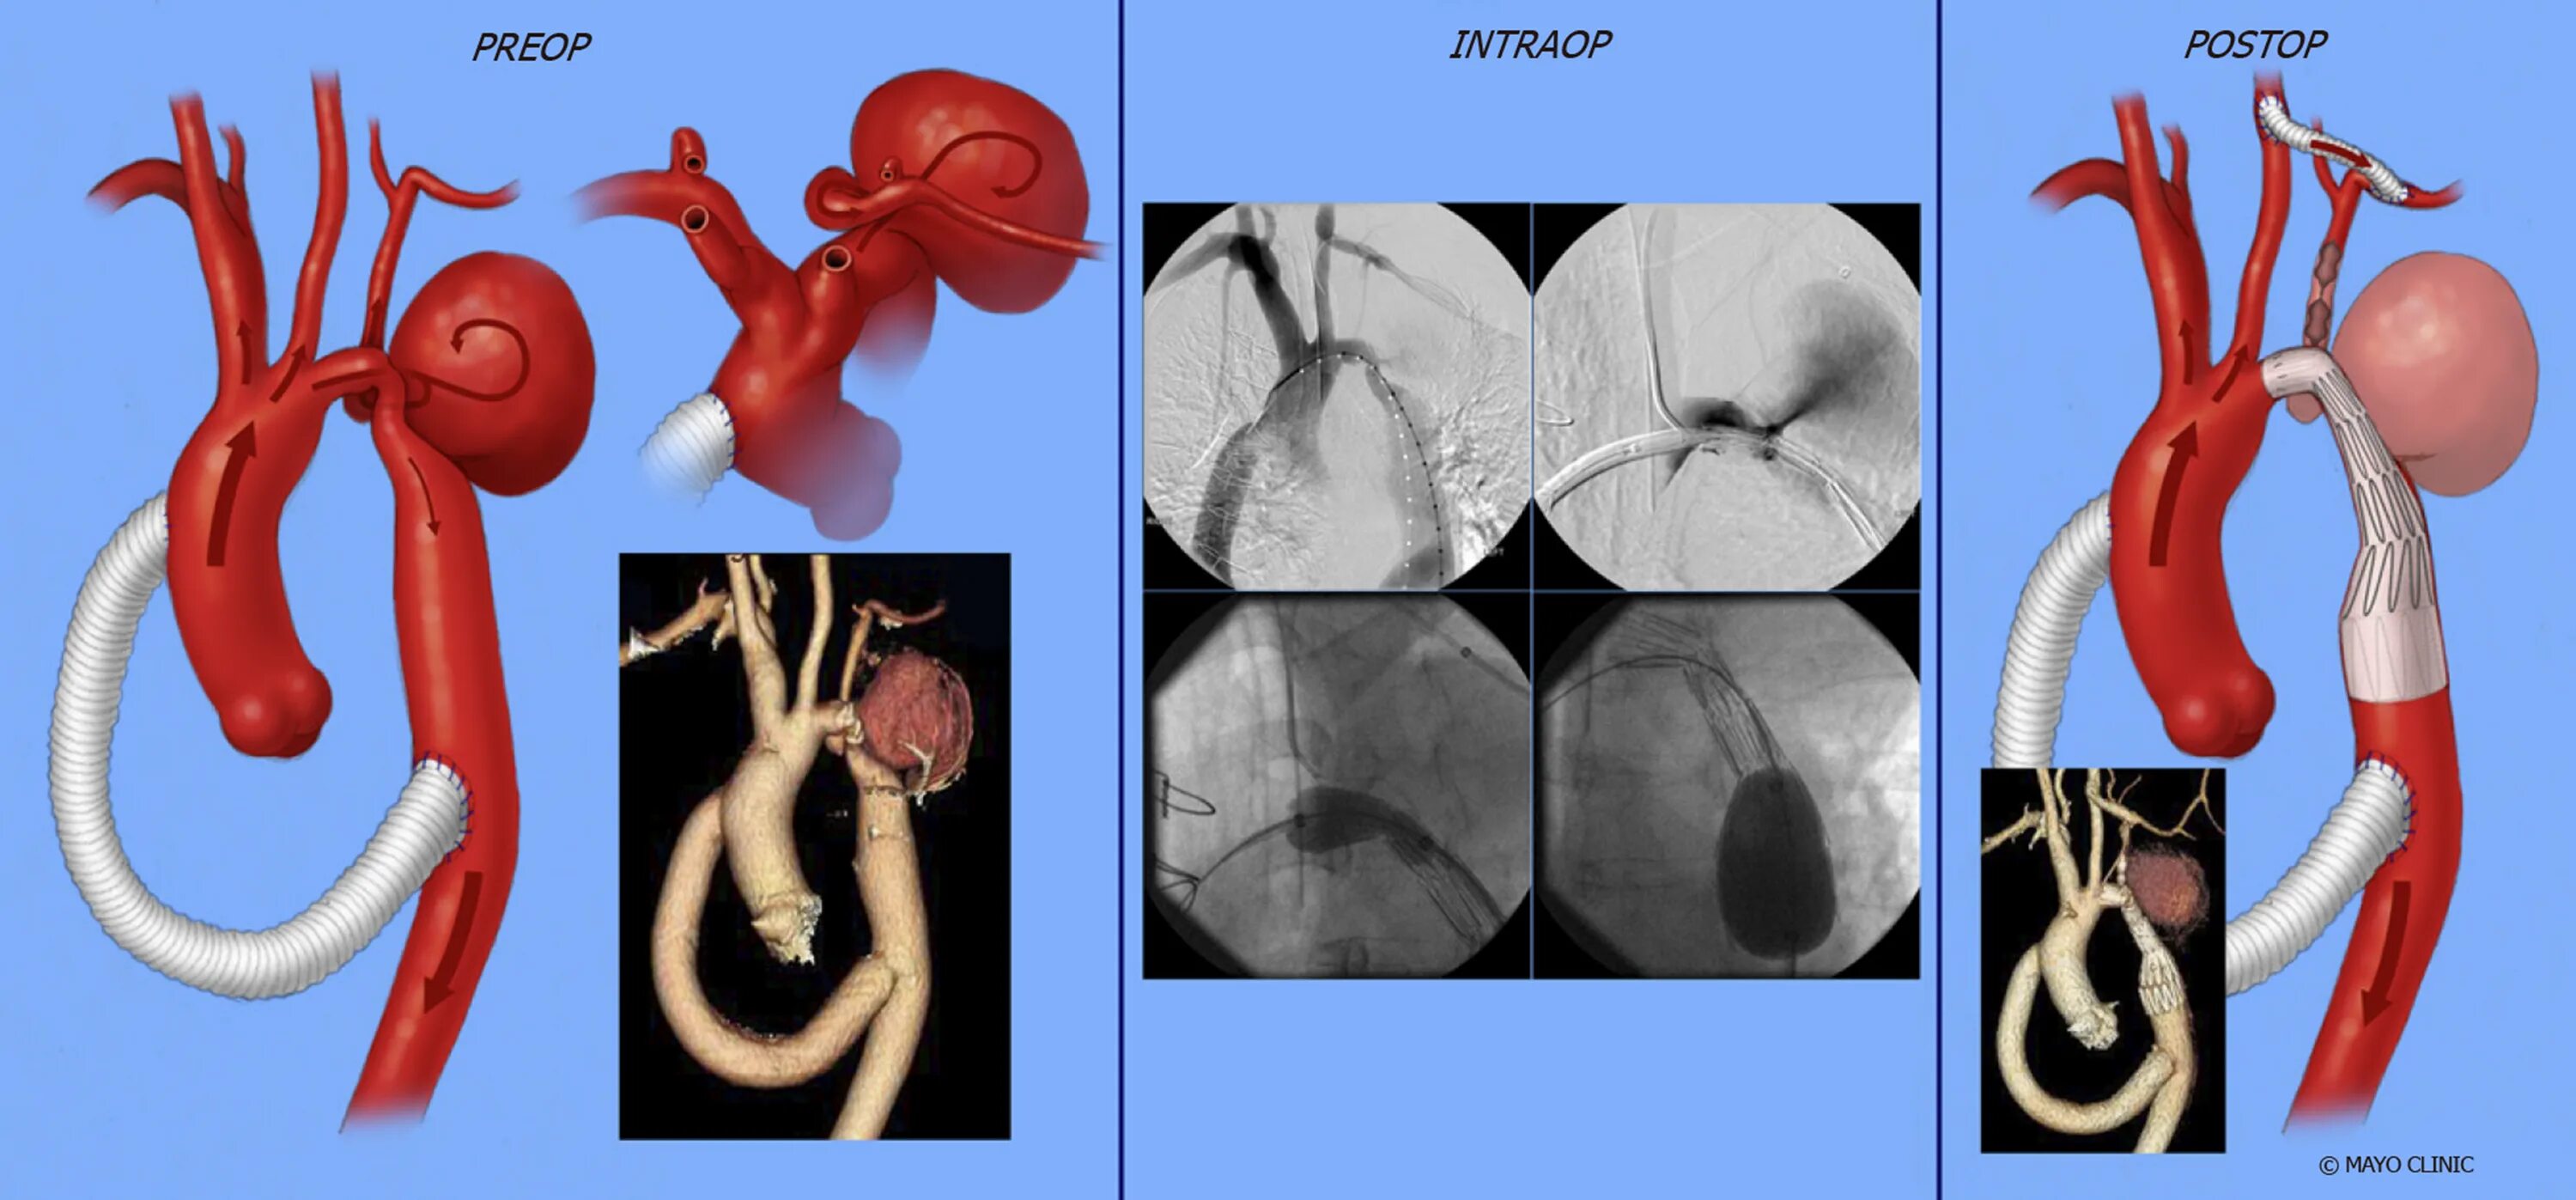

Аневризма аорты мкб 10